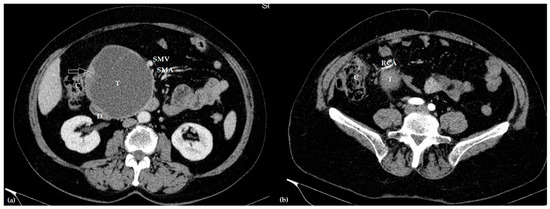

Figure 1. Contrast-enhanced axial computed tomography of the venous (a) and arterial (b) phase showing a large invasive intraductal papillary mucinous neoplasm (T), invading the duodenum (D) and right colic artery (RCA), and in close relationship with the superior mesenteric vein (SMV) and artery (SMA), and ascending colon (C) (the white arrow marks the malignant part of the tumor, without interface with the ascending colon).